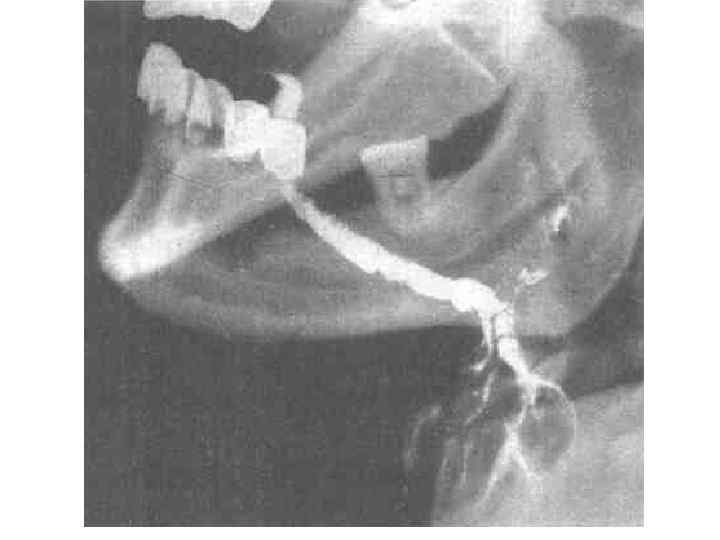

• Методика исследования жевания называется мастикациографией, • прибор, фиксирующий жевательные движения - мастикациограф.

Мастикациография

Электромиомастикациография

Фазы жевания (мастикациограммы) 1. 2. 3. 4. 5. Покоя Введения пищи Ориентировочная Основная Формирования пищевого комка